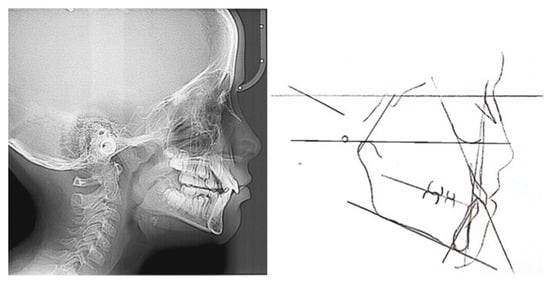

2.3. Cephalometric Analysis

3.2. Cephalometric Values after One Year of Treatment

| Values | |||

|---|---|---|---|

| Before | After | Normal | |

| SNA angle | 78° | 78° | 82 ± 2° |

| SNB angle | 70° | 74° | 80 ± 2° |

| ANB angle | 8° | 4° | 80 ± 2° |

| N-Pg ^ PF | 78° | 79° | 87 ± 3° |

| FMA angle | 23° | 25° | 25 ± 3° |

| Is ^ PF angle | 114° | 109 | 105–110° |

| IMPA angle | 107° | 111° | 90 ± 5° |

| Over jet | +6 | +3 | 2.5 ± 2.5 mm |

| Over bite | +4.5 | +2.5 | 2.5 ± 2.5 mm |